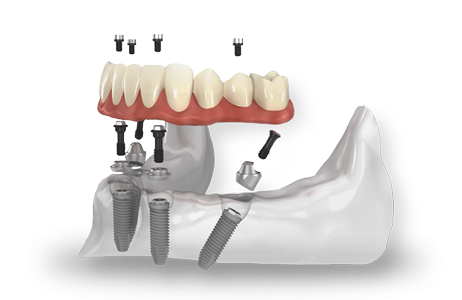

Con questa tecnica si abolisce l’impiego di protesi mobili per realizzare una protesi fissa formata da 10-12 denti in ceramica o in titanio ,sia sull’arcata dentale superiore che su quella inferiore, agganciandola solamente su quattro impianti dentali endossei opportunamente distribuiti.

L’intervento all on four è definito a carico immediato in quanto l’inserimento dell’impianto o degli impianti, realizzati in titanio, su cui saranno fissati i denti fissi avviene in giornata garantendo ai pazienti sia l’immediata funzionalità mandibolare, grazie ad una protesi provvisoria, che la riabilitazione veloce.

L’implantologia a carico immediato all on four utilizza impianti dentali inclinati tra i 30 ed i 45 gradi allo scopo di assicurare un solido appoggio alla protesi dentale.